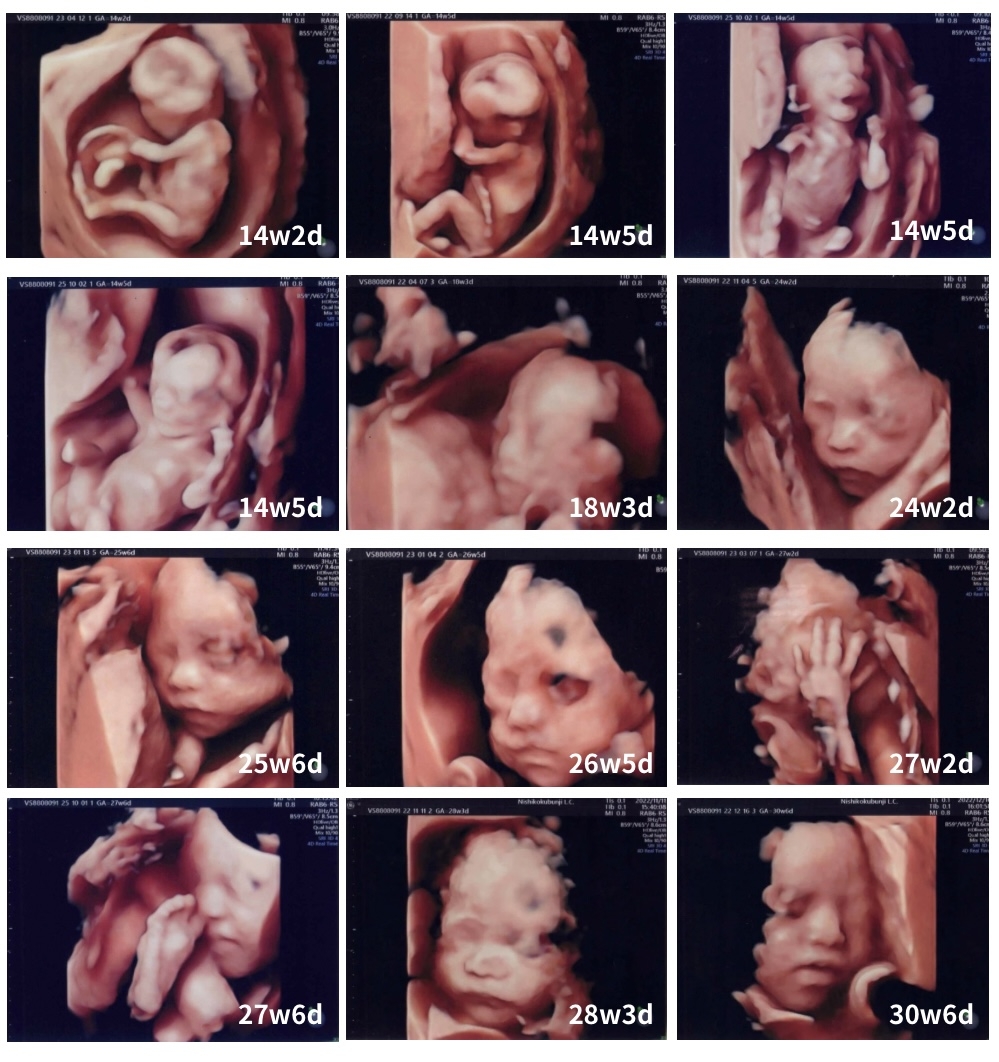

当院の4Dエコー撮影

当院では14週の妊婦健診から毎回4Dエコー撮影を行っております。最新のGE社製の上位機種4D超音波装置(Volson S8)を導入しており、妊娠経過を詳しく見ていきます。胎児エコー像を初期よりUSBメモリーに録画して、ご自宅のパソコンで鑑賞していただくことができます。

4Dエコーでは、赤ちゃんはこの様に撮影できます。院長の解説イラスト入りのお写真を複数枚無料でお渡ししています。